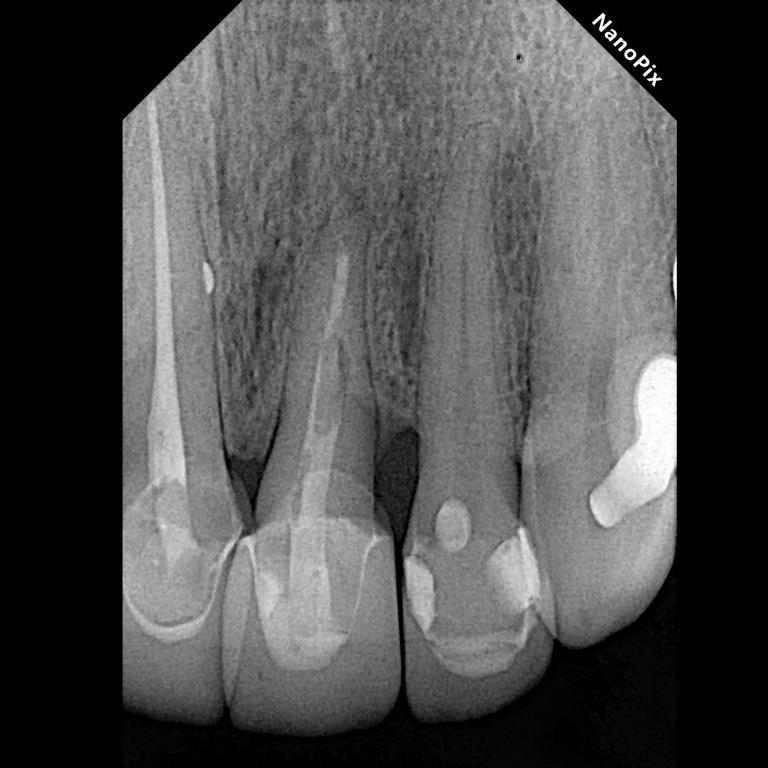

После снятия металлофарфоровой коронки и дезинфекции пораженного участка GLUCOHEX 2% (CERKAMED), была выполнена синдесмотомия скальпелем № 15с с последующим вывихиванием корня с помощью небольшого периотома. Усилие вывиха было приложено только к первым 3 мм корешковой структуры с мезиальной стороны, чтобы избежать повреждения периодонтальной связки, которая должна была оставаться в подкостном положении. Как только зуб был расшатан, его выдвинули примерно на 6 мм и повернули на 180° (фото 2). Ротация была произведена с целью расположения здоровых волокон периодонтальной связки в дистальной области, поскольку в этом месте уже был косой дефект гребневой кости. Обычно во время такой процедуры кость следует за вытянутыми волокнами периодонтальной связки, что делает возможным вертикальное наращивание кости. Ротация также позволила ограничить степень выдавливания. Экструзию и ротацию осуществляли с помощью щипцов, захватывая только коронковую часть зуба, которая после лечения должна была оставаться в надкостничном положении.

Когда зуб достиг желаемого положения, было произведено легкое надавливание в лабио-палатальном направлении с помощью марли, смоченной хлоргексидином, для достижения гемостаза перед шинированием зуба. Для стабилизации зуба было решено использовать нейлоновую моноволоконную нить диаметром 1 мм. Это решение было основано на его экономической эффективности, доступности и гибкости при шинировании, и поверхность, не удерживающая зубной налет, способствует поддержанию надлежащей гигиены полости рта пациентом. Шина была наложена с использованием текучего гибридного светоотверждаемого композита с содержанием наночастиц Nexcomp Flow (Meta Biomed) и двухэтапного адгезивного протокола EZ Bond Universal (Meta Biomed). Продолжительность шинирования было запланировано на три недели, как рекомендовано для достижения стабильности зубов и минимизации риска анкилоза. В литературе указывается, что подвижность значительно снижается через две-четыре недели после снятия шины. Пациентке были даны инструкции по гигиене полости рта и рекомендовано пользоваться мягкой зубной щеткой, чтобы не нарушать заживление десен.

Во время второго визита, через три недели после экструзии, была проведена повторная нехирургическая операция с фиксацией шины. На том же приеме был установлен волоконный штифт, обеспечивающий достаточную высоту сердцевины. Штифт был зацементирован с использованием цемента с двойной полимеризацией смолы, который одновременно использовался для восстановления коронковой структуры. Перед корональным наращиванием шина была удалена.